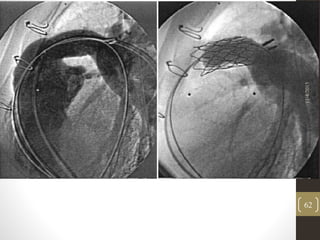

• Femoral vein is dilated to 24Fr

• Delivery system advanced into the RVOT

• Retraction of the sheath from the valved stent

• Contrast injection for confirmation of the position

• Partial deployment by hand inflation of inner balloon.

• Final deployment by outer balloon inflation.

• Deflation of the balloons and the delivery system is withdrawn.

• Post dilation of the valve –discretion of the operator.

11/4/2015

61

62

Modification of the technique

• Predilation and bare stenting of the conduit

• Looping of the system within the right atrium

• Partial retraction of the sheath.

• Repositioning of the guidewire in the contralateral branch

pulmonary artery.

• Post dilation of the device – no damage to valve leaflets or

affect valve competency.